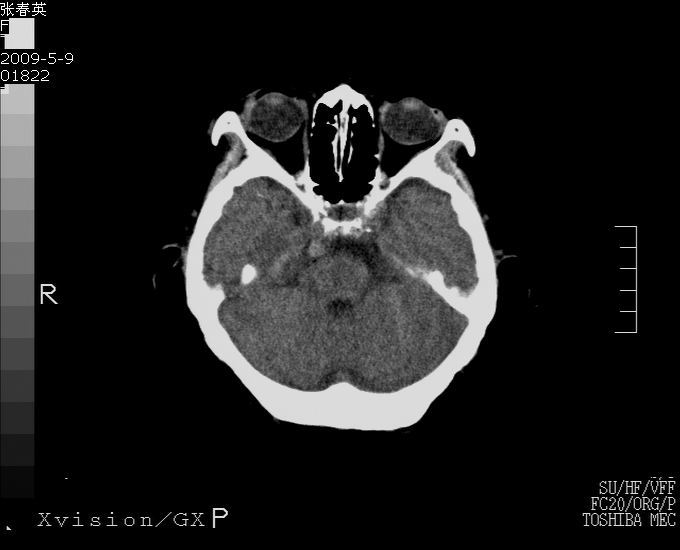

以下是引用余辉在2009-5-9 18:32:00的发言:[br]基底动脉稍扩张且右偏,其上方层面见高密度块影,考虑动脉瘤可能,建议增强,皮脑

以下是引用杀毒软件在2009-5-9 17:48:00的发言:[br]不排除动脉瘤可能,建议进一步检查。 [br]